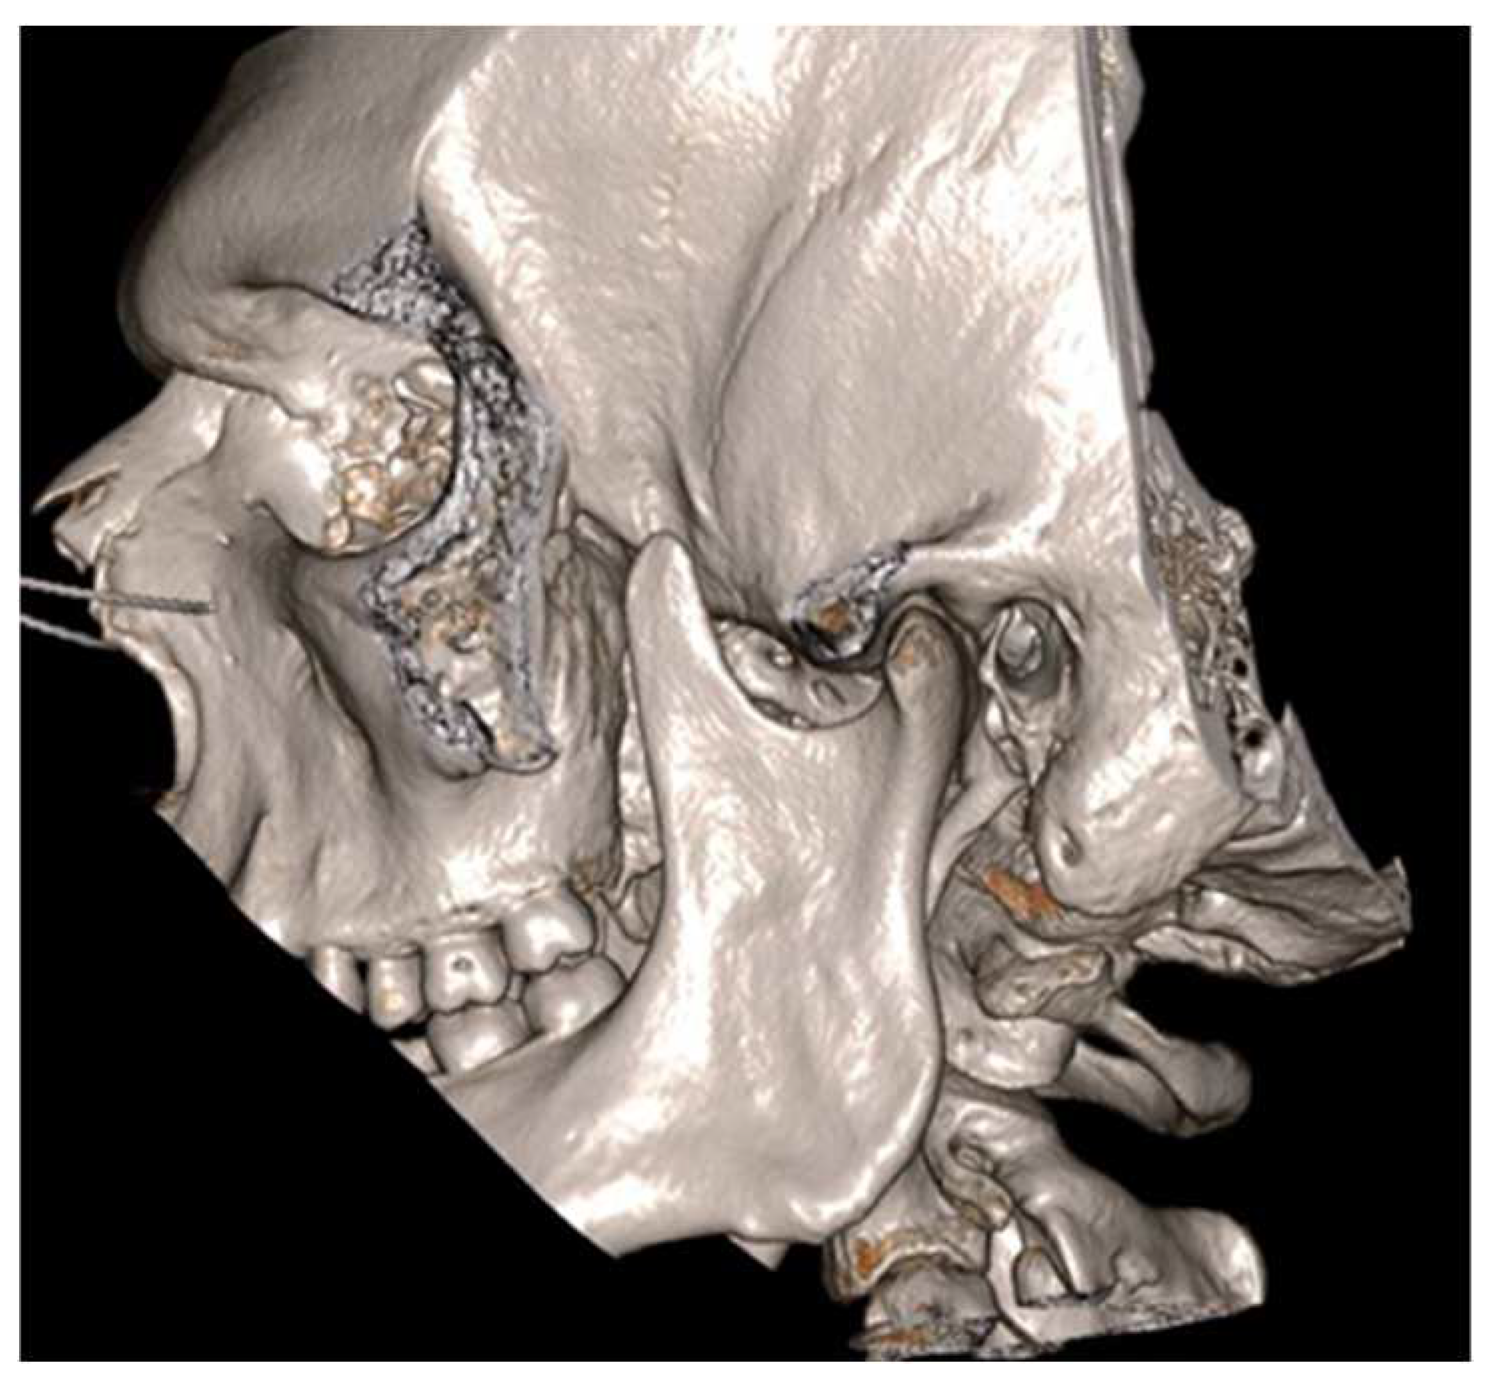

Figure 1.

Patient’s OPG showing no evident anomalies.